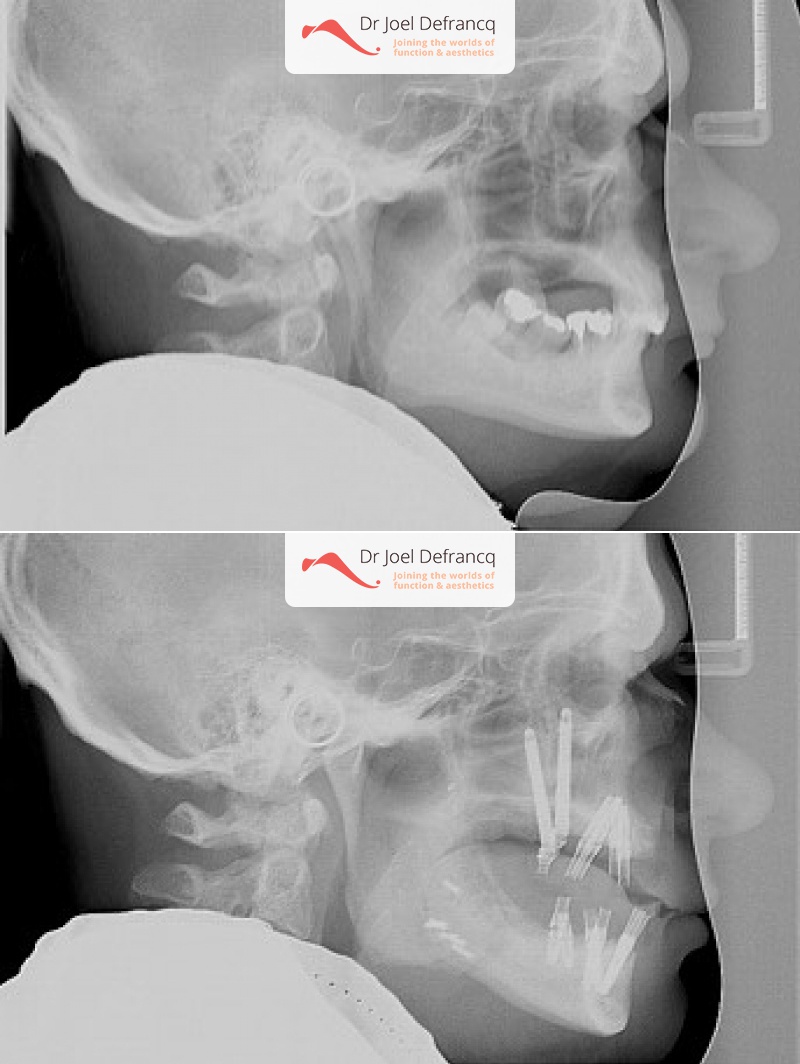

Vigor: Slaapapneu, te korte bovenkaak, overbeet diepe beet, tandimplantaten all on four

Diagnose van het gezicht

- Te kleine onderkaak (Overbeet)

- Te kleine bovenkaak

- Te kort gezicht

Kaakchirurgie

- Verlenging onderkaak (BSSO)

- Verlenging bovenkaak (Le Fort I)

- Vertikale verlenging bovenkaak (Le Fort I)